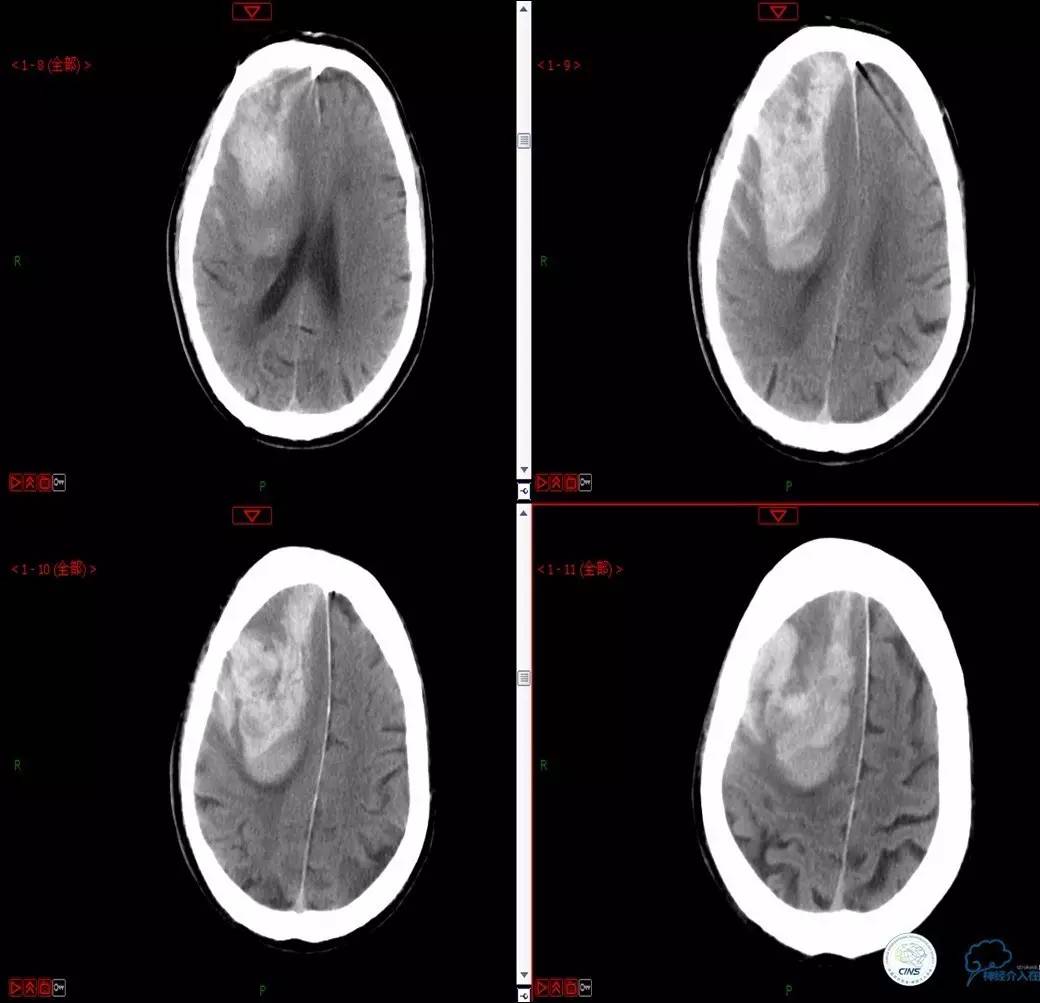

Case 3

》男,79岁。

》主诉:阵发性头晕伴双下肢无力一年余。

》查体:左侧上肢肌力Ⅱ级, 双侧下肢肌力Ⅲ级。

》既往史:高血压、糖尿病史。

》术后严密控制血压,未出现明显血压波动。

》术后三小时,患者出现恶心呕吐,伴有意识丧失。

》出血原因?侧支代偿不佳!